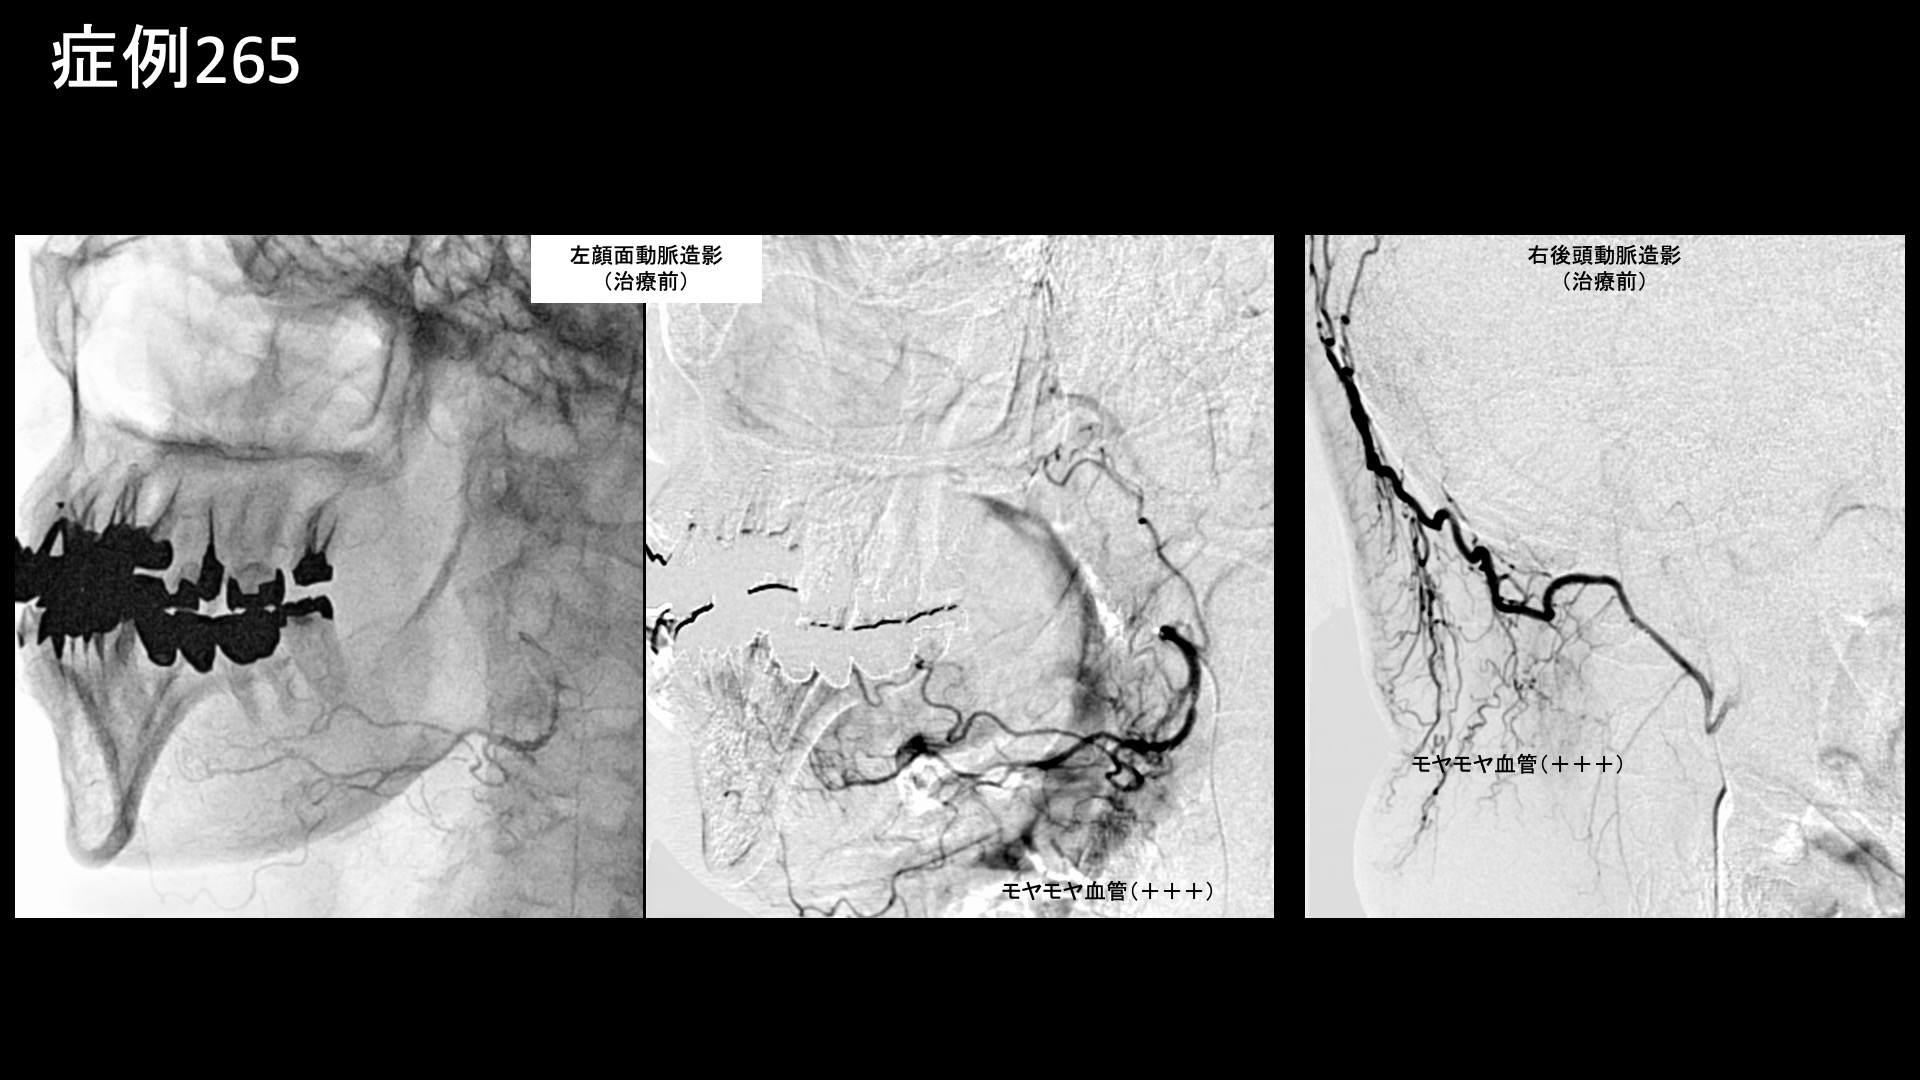

治療後1週間、まだはっきりとした変化は感じられないものの、肩甲骨の周りが動くようになった感じがしました。治療後2週間、肩甲骨がよく動くようになりました。頭痛はまだ変化がありませんでした。治療後1ヶ月、まだ首の重い感じが残っていました。治療後1ヶ月半、頭痛が軽減されてきたものの、首肩はまだドヨーンとしていました。効果は十分感じられたものの、一定の症状が残っていること、実は顎関節症(カクカクいっている)や食いしばり、頭重感もあるため、頭部顔面の治療も併せて追加治療を受けたいとご希望されたため、治療後3ヶ月で追加治療を行いました。まず、前回最も悪かった左頸部の血管造影を行いました。すると、モヤモヤ血管は大幅に減少し、血行が劇的に改善している様子が見て取れました。病的新生血管がモヤモヤ血管のような形で視認できるのは一部であり、この状態でも全く無いわけではありません。初回治療後も必ずある程度は残存していますし、新たに生じてくるものもあります。追加治療を行う意義は、初回時には到達しにくかった部位に薬液が到達できる利点も含めて、病的新生血管をさらに減少させるところにあります。前回同様部位を治療した後、続いて頭部・顔面の治療に入りました。左顔面動脈や右後頭動脈にてモヤモヤ血管が濃染像として描出されました。治療後は画像上速やかに消失しました。その他複数箇所の治療を行い終了しました。追加治療から1ヶ月後、常にあった頭重感が無くなりました。治療後2週間くらいから改善したようですが、すごく楽になったので、いつから楽になったかも覚えていないほどと言われました。しばらく他部位の治療のために通院を続けていましたが、首肩も同様に改善が進み、加療不要となりました。元々積極的に運動をされる方で、ご自身で再発予防に取り組まれていたこともあり、特にぶり返すことなく、治療後5ヶ月で終診となりました。